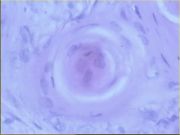

| 2021年12月10日 (五) 13:17 | 16号切片-鳞癌(角化珠)-镜下观2.jpg (文件) |  |

66 KB | Cirno.9 | 基于MsUpload的文件上传 | 1 |

| 2021年12月10日 (五) 13:17 | 16号切片-鳞癌(角化珠)-镜下观1.jpg (文件) |  |

80 KB | Cirno.9 | 基于MsUpload的文件上传 | 1 |